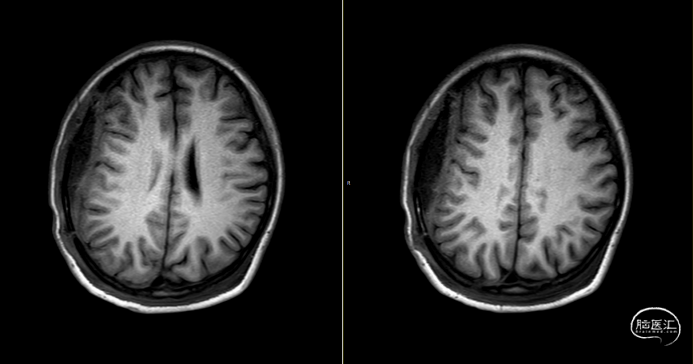

第2次术后12天,仍有间断头痛,刀口愈合可,复查颅脑MRI(如上图):右侧额顶颞部软组织稍增厚,右侧额顶部颅板下见条片状长T1、长T2信号,T2FLAIR呈稍高信号,边界清,DWI(b=1000)呈混杂高信号,相应ADC呈混杂高信号影,加用美罗培南联合万古霉素抗炎治疗。